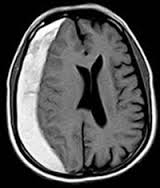

Beynimiz jelatin kıvamında bir dokudur ve beyin omurilik sıvısının içinde adeta yüzmektedir. Bu sıvı ayrıca beynin derininde yer alan ventrikül adı verilen boşlukları doldurmaktadır. Böylece beyin sarsıntıdan etkilenmez ve beyin omurilik sıvısı içinde batmaz bir şekilde yüzmektedir.

Beyin omurilik sıvısı ventriküller boyunca birbiriyle bağlantı yapan kanallar sayesinde devirdaim yapmaktadır.

Beyin omurilik sıvısının üretim, akım ve emilim süreci arasındaki varolan hassas denge, sıvının kafa içerisinde normal basınç altında devirdaim yapabilmesi açısından çok önemlidir. İşte hidrosefali denilen klinik tablo bu hassas dengenin bozulması durumunda ortaya çıkar. Örneğin ventriküller arasında geçişi sağlayan kanalların daralması veya sıvının emilmesinde bir hasar olması gibi sıvının devirdaimi sürecinde herhangi bir basamakta aksama olması hidrosefali oluşumuna neden olmaktadır.

Doktorunuz semptom ve bulguları değerlendirdiğinde hidrosefaliden şüphelenirse tanıyı koymadan önce ayrıntılı bir şekilde hastalığın gidişatını öğrenmeli, ayrıntılı bir fiziksel ve nörolojik inceleme yapmalı, CT veya MRG ile görüntüleme yapmalıdır. Tetkikler sonucunda hidrosefali teşhisi konursa hasta daha ileri tetkik ve tedavi için beyin cerrahi uzmanına refere edilmeli.